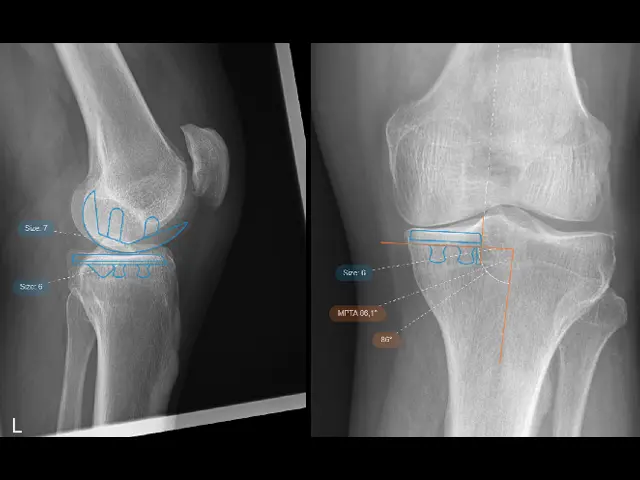

4. Digital surgical planning: Based on this detailed data, we plan the optimal size and position of your prosthesis. This allows us to proceed with a customized plan that is accurate to the millimeter.